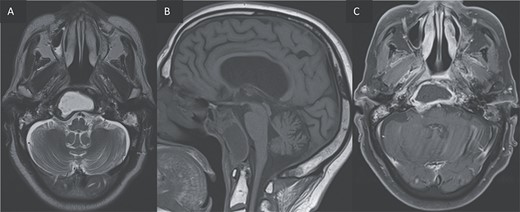

A computed tomography (CT) scan with intravenous contrast was performed (Figs 1 and 2), it revealed:

A 3 × 2.5 × 3.2 cm low-attenuating intra clival mass with peripheral enhancing, accompanied by extensive bone erosion of the clivus.

Bone destruction extending to the petrous, tympanic, and mastoid portions of the temporal bone, with involvement of the body and right greater wing of the sphenoid as well as the occipital bone, and concomitant sequestrum formations within the necrotic bones.

Presence of soft tissue in the middle ear cavity and in the mastoid cells.

(A) Axial CT in soft-tissue window showing an intra clival fluid collection (star). (B) Axial Post contrast CT showing a peripheral enhancement (arrow).